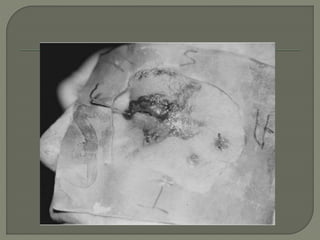

 Typical lesions are round-to-irregular, plaquelike

 nodular, and overlaid with a warty keratotic

scale or conical keratinized cutaneous horn.

 Surrounding erythema may be present, and

bleeding results from minimal trauma

 usually superficial, invasion of the subcutis does

occur with muscle invasion and extension along

periosteal, perineural, and angiolymphatic

channels.

• #23 Well-differentiated squamous cell carcinoma of the skin invading deeply into the dermis. The malignant cells are pleomorphic and exhibit many mitoses